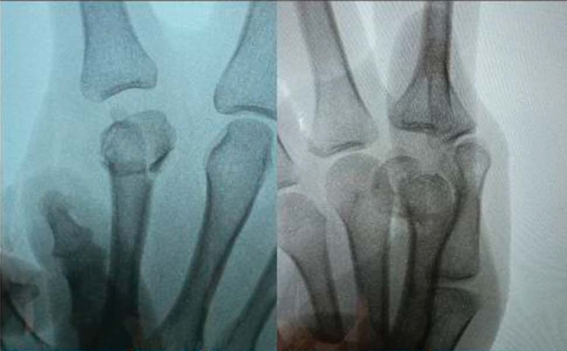

1. Percutaneous Screw Fixation for Metacarpal Head Fractures